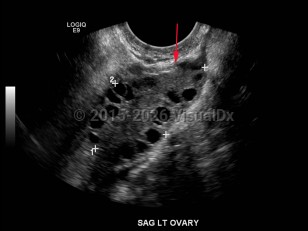

Polycystic ovarian syndromePolycystic ovarian syndrome